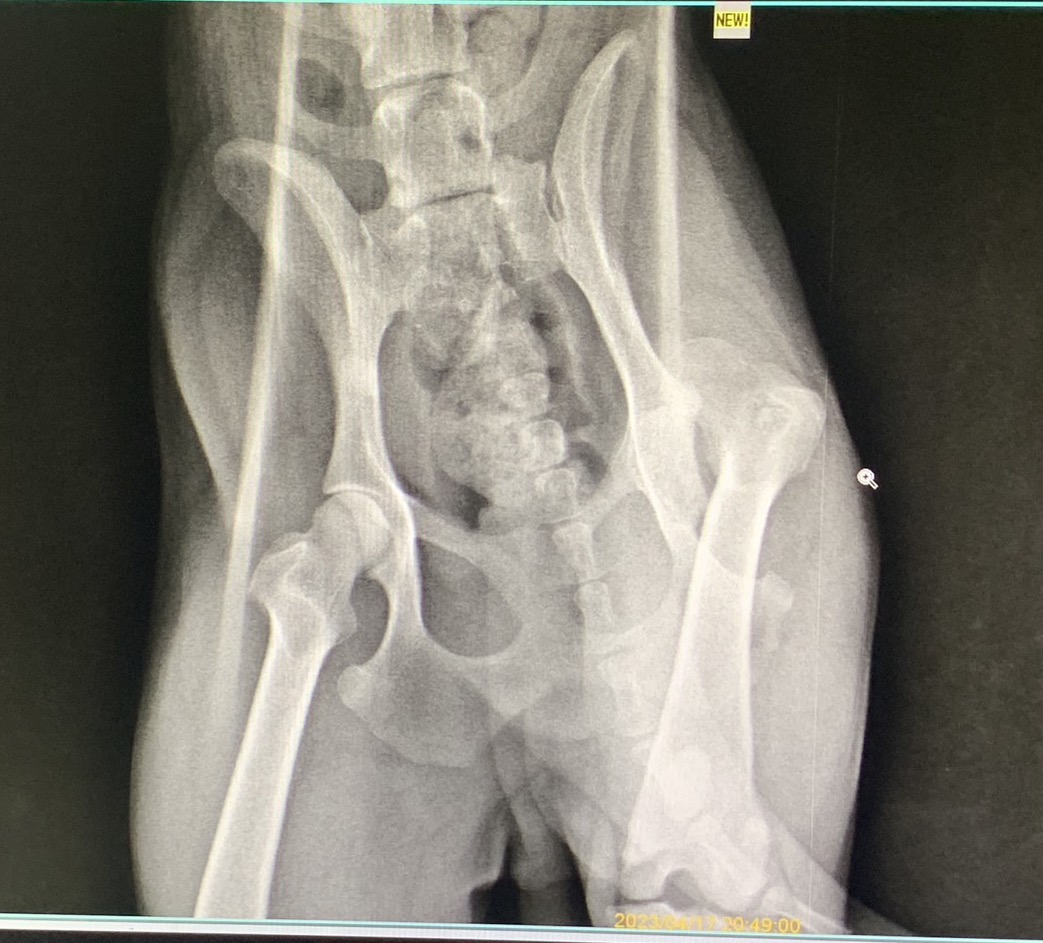

十年前10隻裡只有1隻會有關節遺傳的問題,但現在已變成10隻裡會有5-6隻,

更讓骨科專科流行到一個巔峰,新養一隻幼柴就必需先檢查關節的地步。

再來就是70%的柴犬都會遇到的關節問題.jpg)

適用柴犬:以前我會建議7、8歲開始注意,但若是現在的柴犬,最好可以越早越好。而柴犬算是運動量大的犬種,對於軟骨的維持是非常需要注重的問題喔。

可能發生的關節問題:

1、 很興奮的外出散步,突然走一下就會停下來原地休息(不做其它行為);

2、 柴犬突然減少與好朋友跑步追逐。

3、 突然不喜歡跳

注意:天生有關節問題的,請找醫生。

這個配方主要訴求是在於柴犬年紀越來越大時,軟骨物質製造能力下降,軟骨漸漸磨損後產生的關節問題,而這配方除了軟骨外,肌肉也幫你想到了